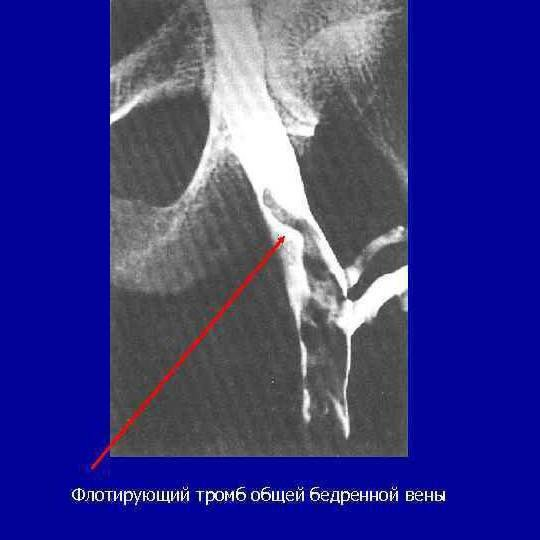

Уже в реанимации провели дуплексное сканирование глубоких вен, которое показало, что практически все вены правой ноги заполнены тромботическими массами. Последующая флебография (введение контрастного вещества в вену) позволила увидеть истинные размеры тромба – он заполнял тазовые, почечные вены и заканчивался в нижней полой вене на уровне мечевидного отростка грудины!

Белое контрастное вещество позволяет контрастировать тромб. На представленной картинке он показан красной стрелкой.

Очевидно, что отрыв даже небольшого фрагмента этого тромба мог стать для пациента фатальным. Хирургически удалить тромб из венозного русла невозможно – не существует таких методик. Поэтому было принято решение о растворении его с помощью тромболитического препарата.